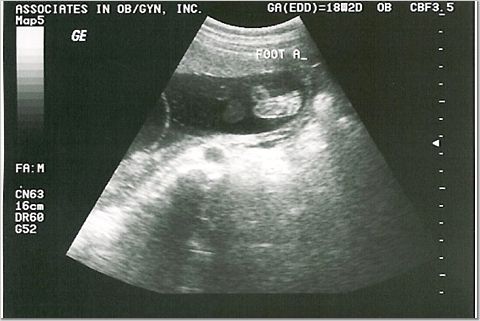

We went to Ultrasona in O'Fallon on Saturday, July 23rd (after the ultrasound with the doctor)

and found out that one of the babies is a girl! We went back on Tuesday, July 26th

and found out they are both girls!

IT'S 2 GIRLS!!!

The "It's a girl" shots.

Right above the "I'm" in the first pic and to the left of the "I'm" in the second pic

are the 3 white lines that indicate girl.